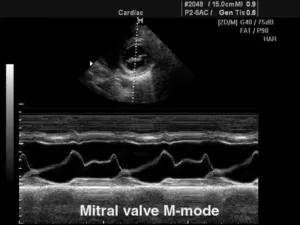

М-режим (отраженный импульсный режим)

M-mode («motion» — движение) — одномерная регистрация отраженного эхосигнала, применяющаяся в кардиологии для изучения сократительной способности миокарда, клапанного аппарата, оценки изменения размеров полостей в систолическую и диастолическую фазы.

В данном режиме оператор сканирует кардиальные структуры только вдоль одной оси. Информация о сигналах с различных глубин изображается в виде отметок различной яркости вдоль вертикальной линии на дисплее. Следующему зондированию соответствует другая линия, расположенная правее предыдущей. В ходе перемещения столбца с каждым новым сканированием записывается двухмерная М-эхограмма.

Существует несколько типов М-режима:

·      M-mode (стандартный): предполагает получение одномерного изображения;

9.jpg

·      Color M-mode (цветной): сочетает стандартный режим и цветовое допплеровское картирование;

11.jpg

·      Free-angle M-mode (анатомический): позволяет произвольно выставлять направление зондирования и визуализировать кардиальные структуры под различным углом.

12.jpg

При неправильном расположении курсора все параметры могут быть завышены, что приведет к неправильной интерпретации полученных данных. Поэтому диагностика в М-режиме требует строгого соблюдения правильной позиции сканирования.

Классический М-режим имеется во всех современных ИЗИ аппаратах, анатомический режим представлен в устройствах более высокого класса. Специальные датчики для обследования в М-режиме не применяются, регистрация М-эхограмм осуществляется датчиками для В-сканирования.